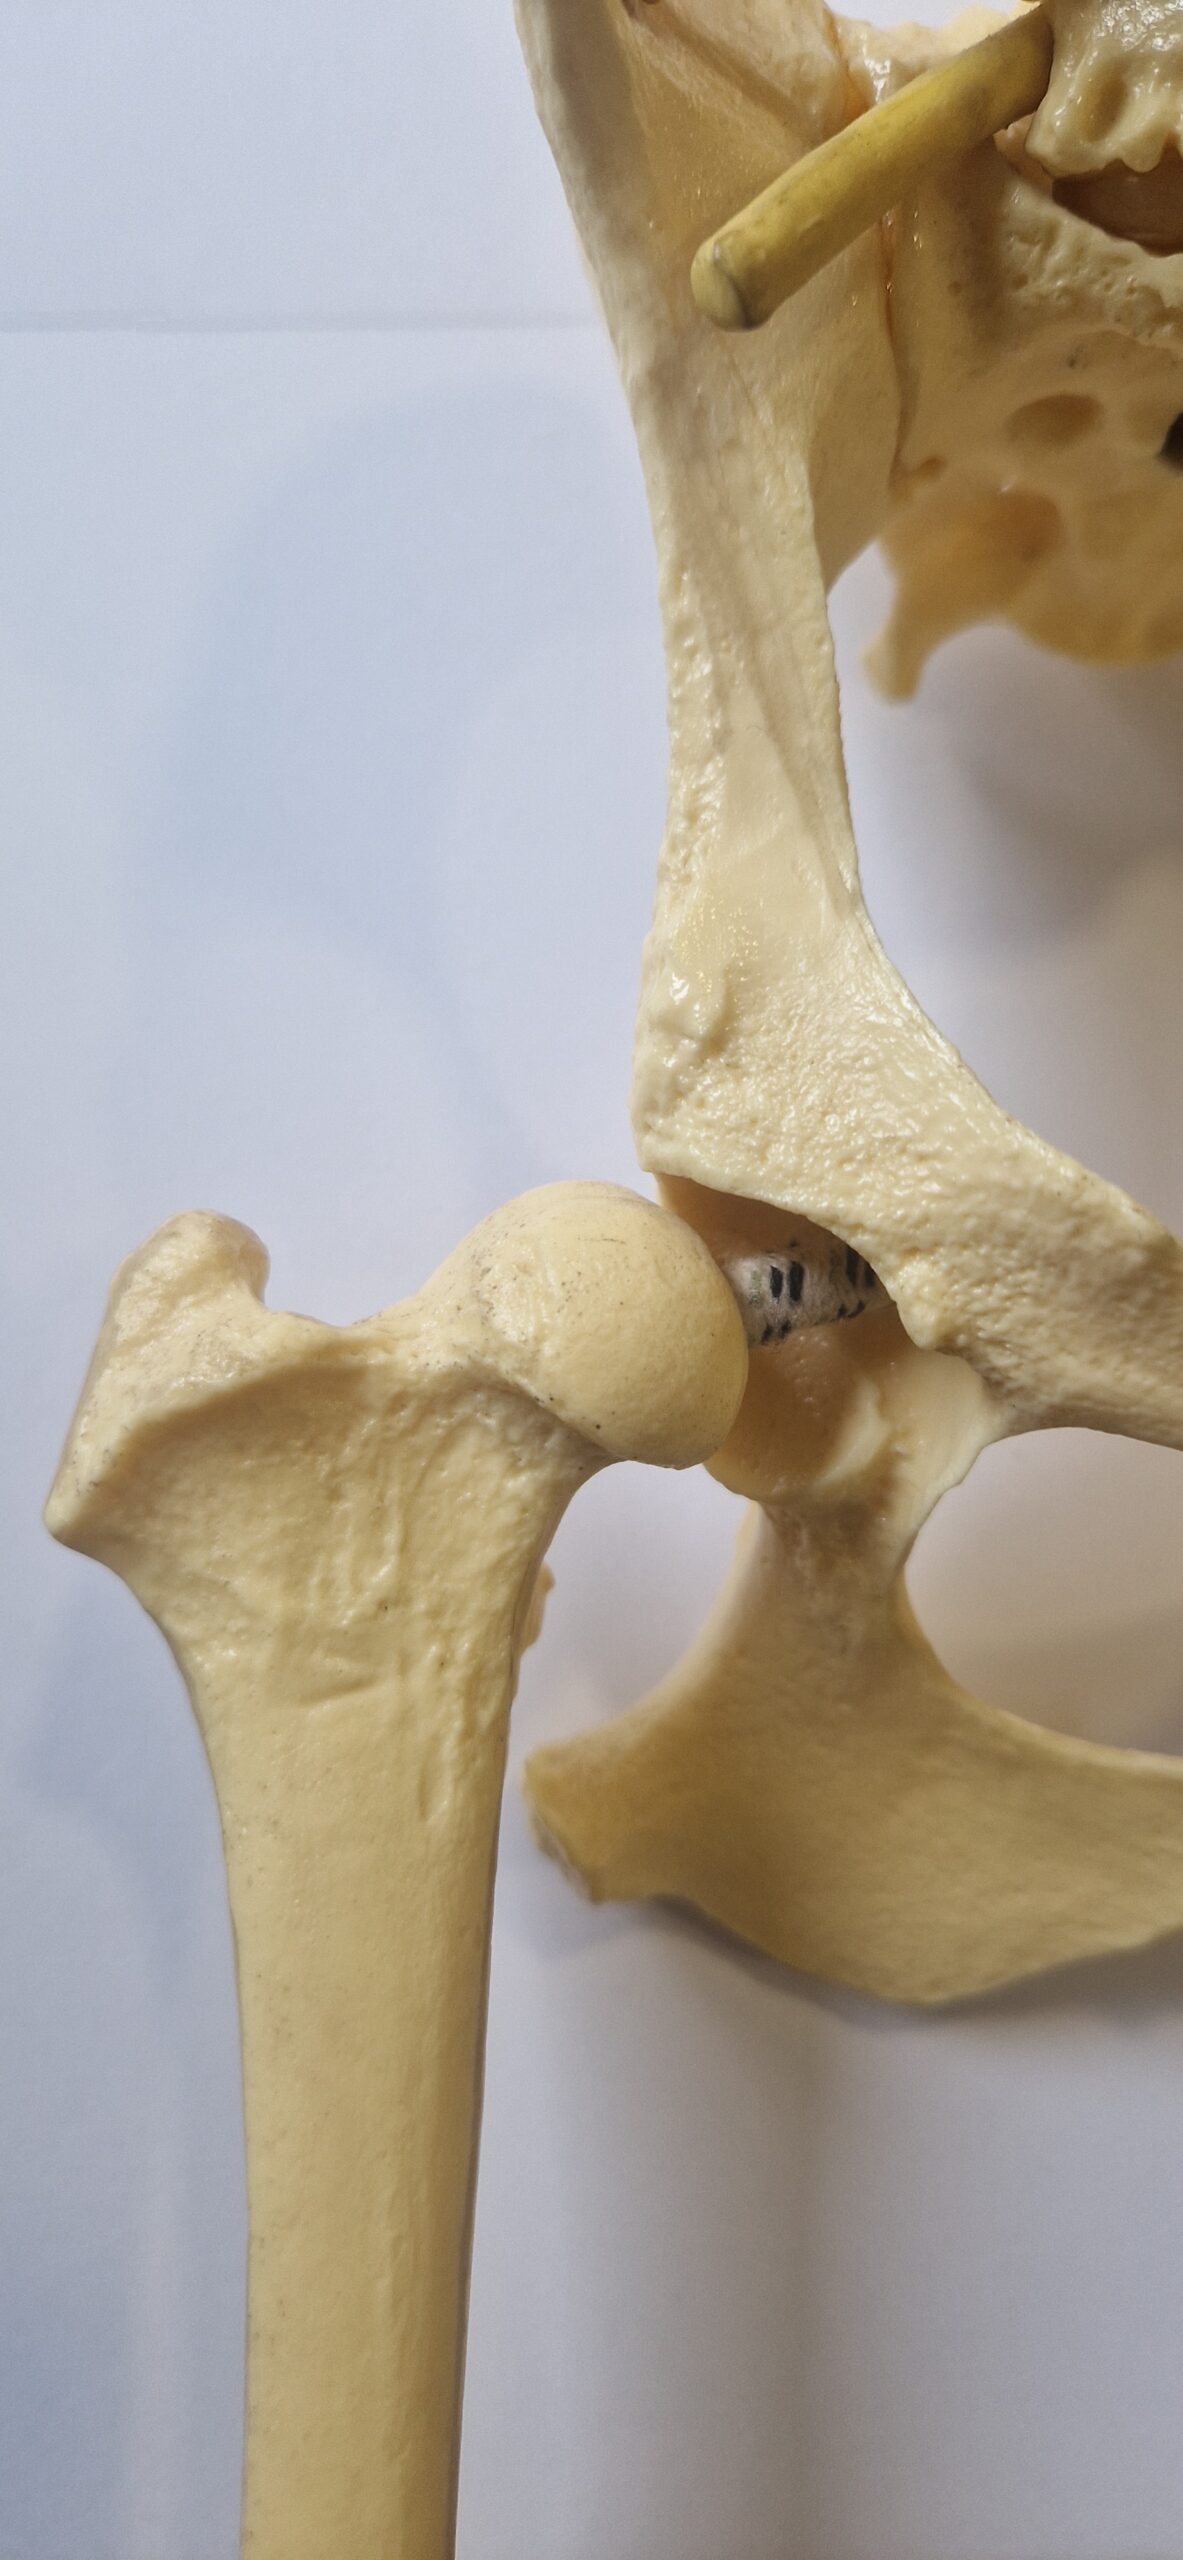

La dysplasie des hanches est une maladie articulaire. L’articulation de la hanche est formé par l’union de deux os, le bassin d’une part, et le fémur d’autre part. L’os du bassin possède deux cavités appelées « acétabulum ». Le fémur se termine en haut de la cuisse par une sphère appelée la « tête du fémur ». Dans les articulations en bonne santé, la tête de fémur va s’emboiter parfaitement dans l’acétabulum du bassin. Par contre chez certains chiens, cette emboitement n’est pas optimal! La tête du fémur est moins arrondie, la cavité du bassin moins bien creusée et recouvre moins bien la tête du fémur… il y a une instabilité plus ou moins marquée dans l’articulation.

hanche idéale

hanche légèrement instable

hanche fortement instable

Comme expliqué plus haut, l’articulation de la hanche est formée par l’union de deux os, l’acétabulum du bassin et la tête du fémur. La tête du fémur est maintenue bien enfoncée dans l’acétabulum par le ligament rond représenté par un large élastique blanc et bleu dans les images plus haut. Chez le chien dysplasique, dès l’âge de 1 mois (eh oui quand il est chiot!) ce ligament rond va prendre un aspect légèrement œdémateux et perdre quelques fibres. Cela va lui procurer une plus grande laxité et rendre l’articulation de la hanche moins stable. La tête du fémur va bouger légèrement dans la cavité acétabulaire. Il va y avoir à chaque mouvement, à chaque choc, des micros-traumatismes sur le cartilage de cette tête fémorale et de la cavité acétabulaire du bassin. Cela va conduire à un remodelage de ces 2 surfaces articulaires. La cavité sera moins creusée, la tête fémorale sera moins ronde. Ces phénomènes vont encore plus accentuer l’instabilité articulaire.